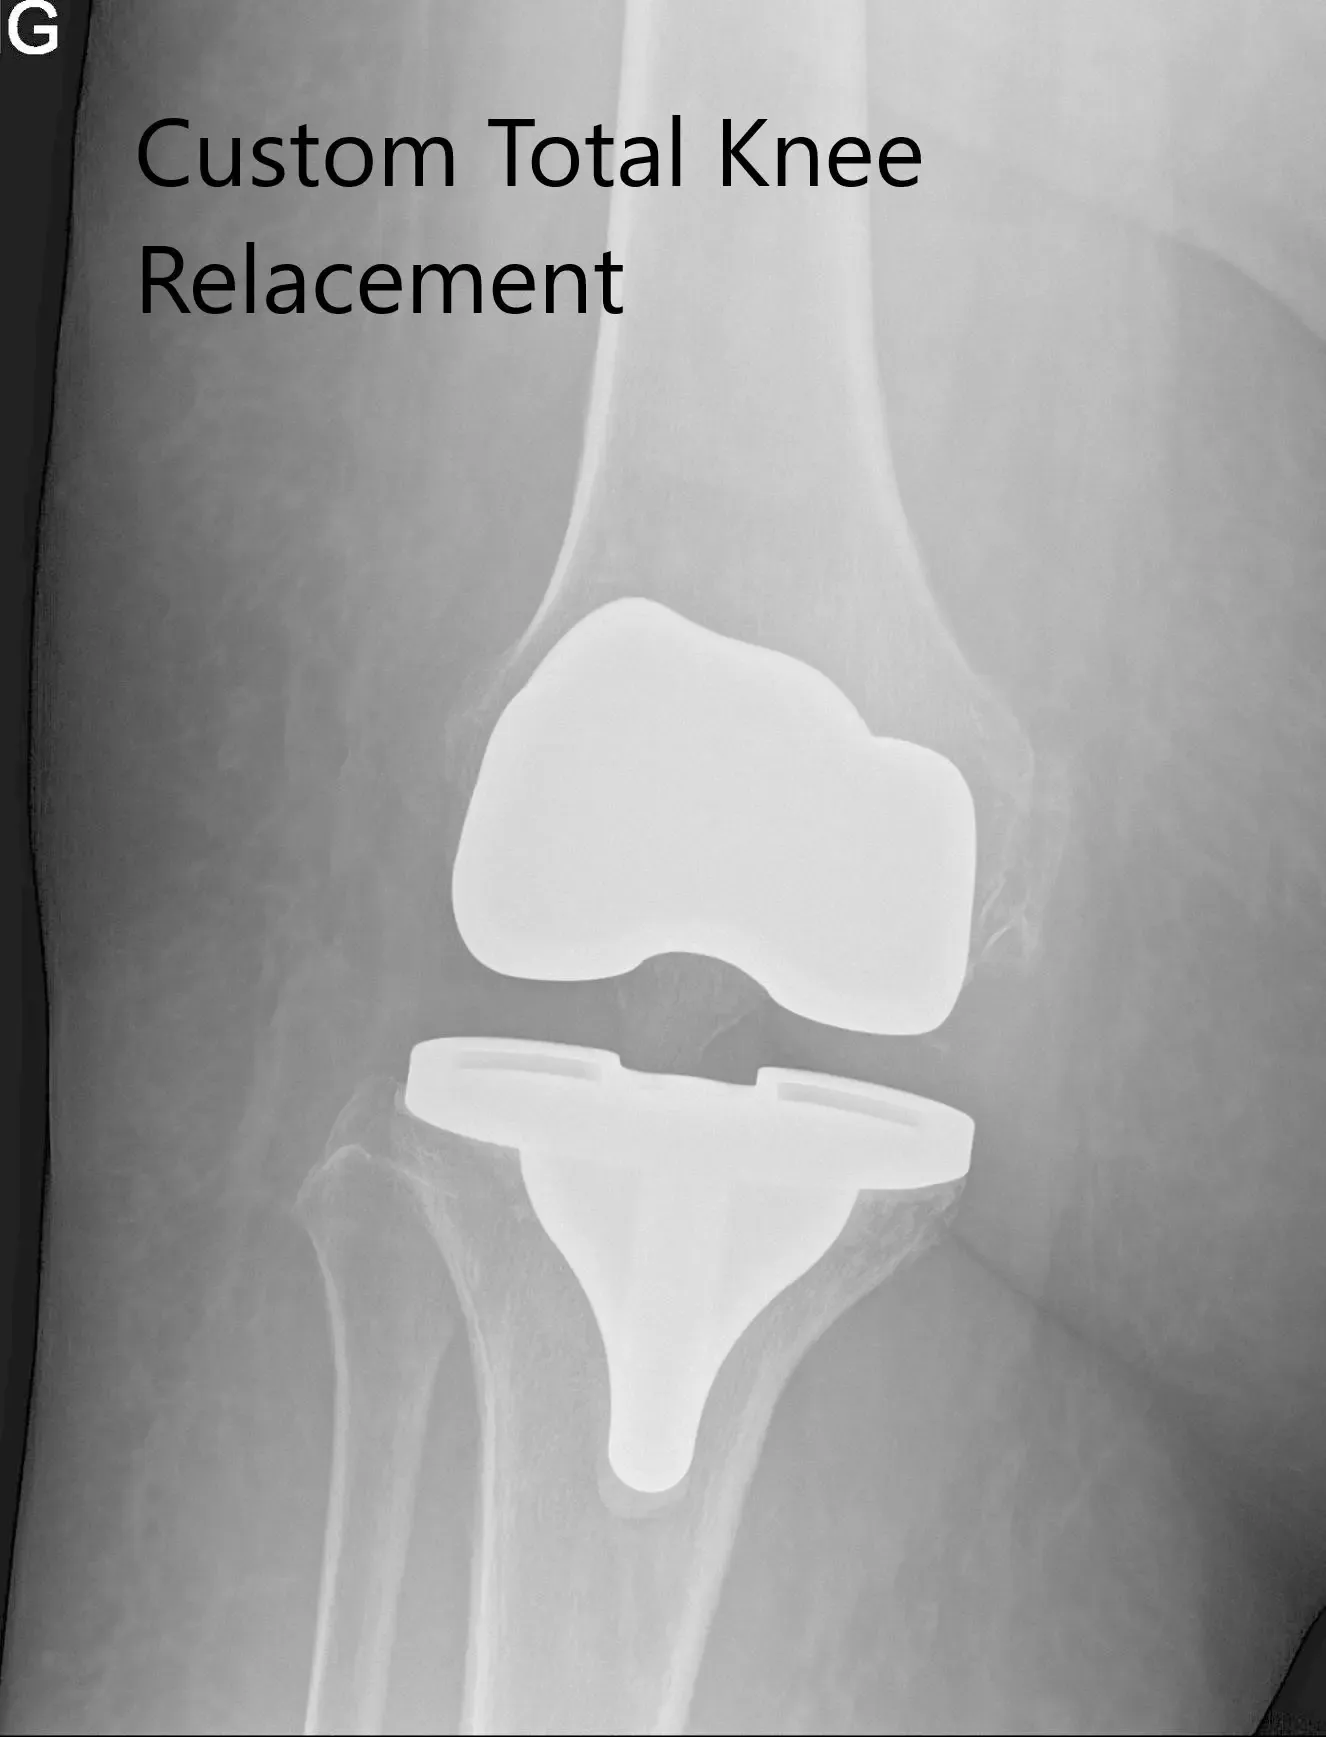

Imágenes de radiografía postoperatorias que muestran la AP y las vistas laterales de la rodilla derecha

Su radiografía postoperatoria mostró una excelente alineación. Se inició fisioterapia ambulatoria para aumentar el rango de movimiento y fortalecer los músculos. En una visita de seguimiento posterior, no mostró dolor ni con un rango de movimiento completo. Volvió a sus actividades habituales y expresó satisfacción por el resultado de la cirugía. Ella hace un seguimiento cuando es necesario.